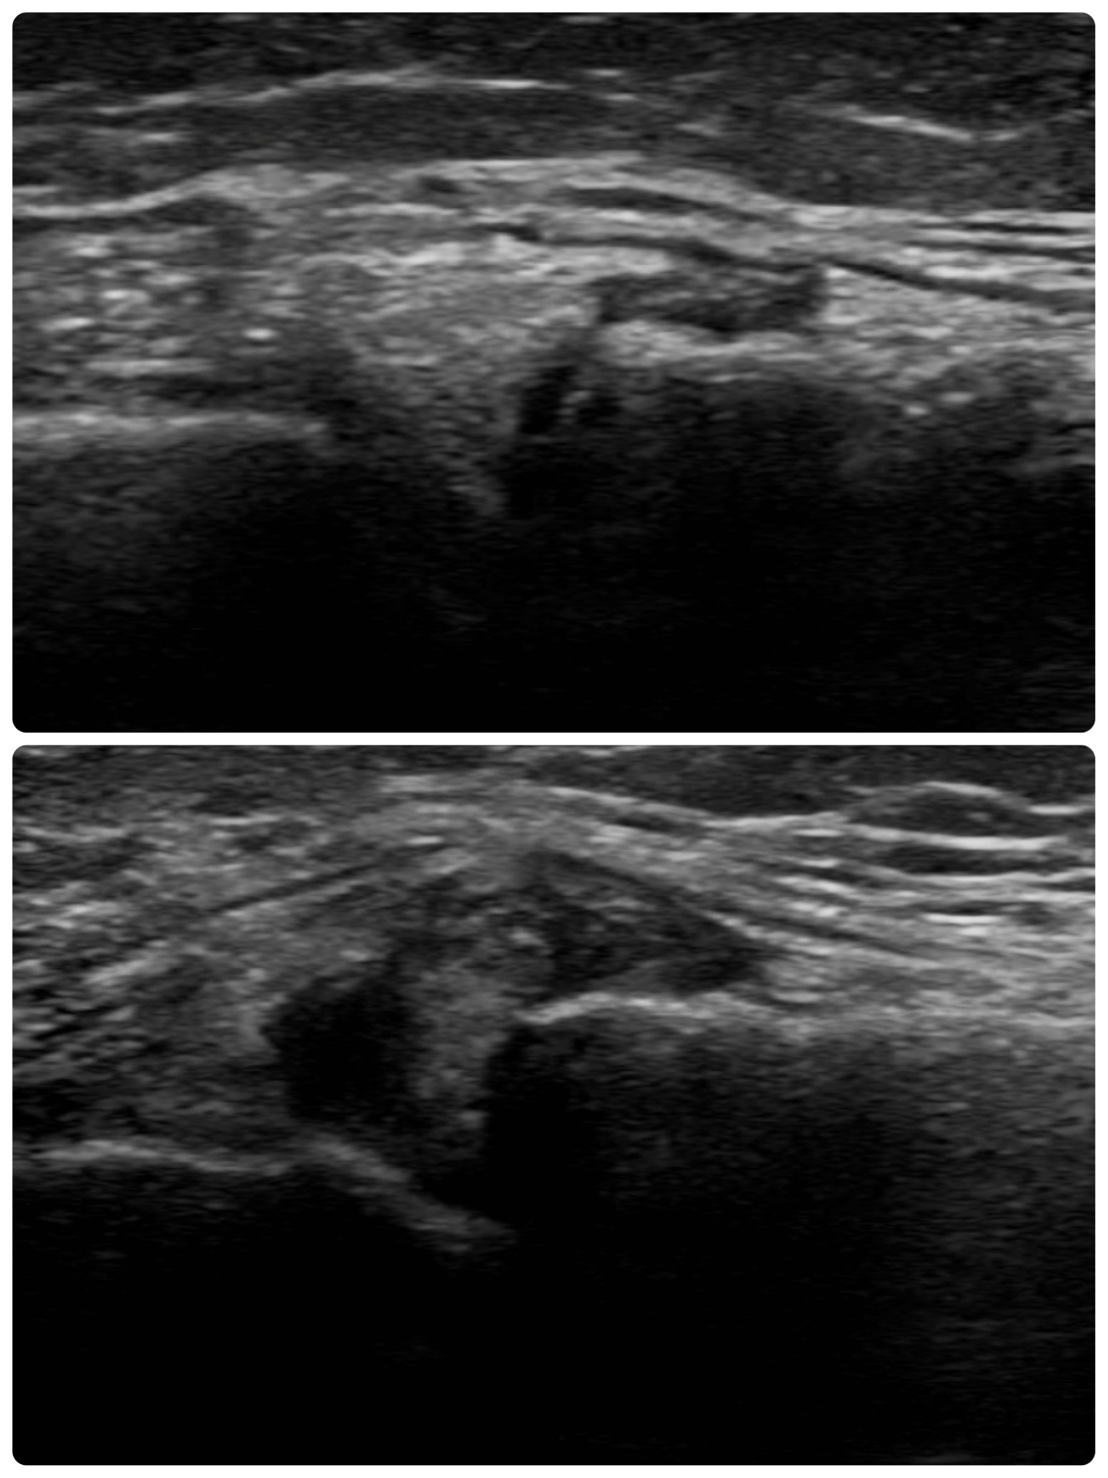

エコーを用いることで、左右差を比べて、構造的な問題を可視化することで安心できる部分もあります。下記の画像は実際の患者さんの膝のエコー画像となります。

これは膝の関節の間の腫れを表しており、下の画像が痛みを感じているところです。可視化することで、なぜ痛みを感じているのかを写しだすことで、安心材料にもなりますし、痛みの原因を知る一つのツールとして活躍します。